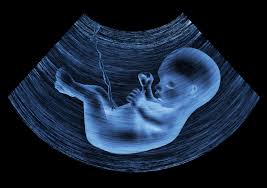

Is an ultrasound picture of a pregnant lady part of her awrah? Is she allowed to show the scan photo to other people or is this considered her awrah and not to be shared?

Ultrasound images are images of which the features are not clearly defined, and the one who looks at them can hardly make anything out, because this refers to an image that is formed from dark and bright spots, the details of which are known to specialists, doctors and others.

Based on that, the image that is produced by ultrasound is not regarded as coming under the heading of ‘awrat that it is haram to uncover and must be concealed. But the matter of dignity and decency is broader than the issue of halal and haram. Based on that, the woman should conceal these images from strangers (non-mahrams), out of a sense of modesty and dignity, because it is not dignified for her to show them to such people, except in the case of necessity or need, such as a doctor who is treating her, for example.